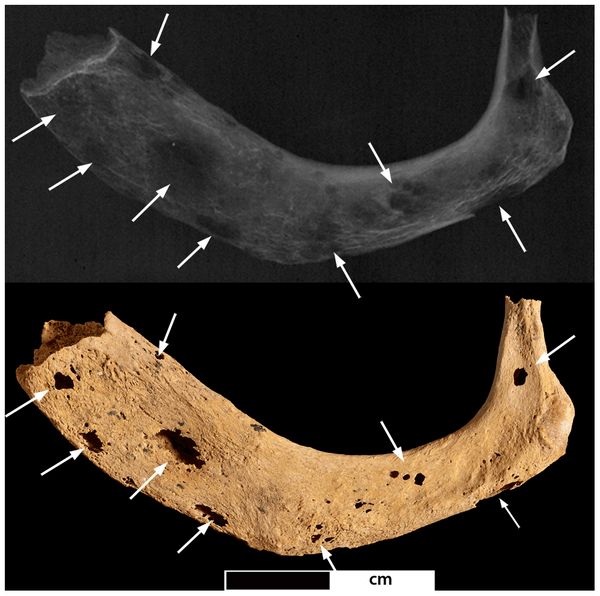

Prima della recente scoperta sudafricana, il più antico tumore maligno osservato in un fossile umano era un cancro presente nella mandibola di un esemplare di Homo ritrovato nel 1932 a Kanam, in Kenya, dal paleontologo britannico Louis Leakey. L’osso risale al Pleistocene e ha un’età di circa 1 milione di anni, ma ci sono ancora dubbi sulla datazione corretta, così come ci sono dubbi sul tipo di tumore presente, identificato dagli studi ogni volta come una neoplasia diversa: da osteosarcoma a linfoma di Burkitt a osteomielite traumatica.

Sono tante le difficoltà che si incontrano quando si cerca di identificare un cancro in un reperto fossile, amplificate anche dal fatto che i frammenti disponibili sono spesso molto piccoli e che si sa poco o nulla sul “paziente”. Solo la tecnologia riesce a trovare risposta a molte delle domande dei “paleoncologi”: nel caso dell’osteosarcoma scoperto in Sud Africa, ad esempio, la diagnosi è stata possibile grazie all’utilizzo di una microtomografia computerizzata a raggi X in grado di generare immagini in due e in tre dimensioni del piccolo campione disponibile. Questa tecnica, unita al confronto con campioni moderni, ha permesso di scartare altre possibili diagnosi e di arrivare al risultato definitivo.